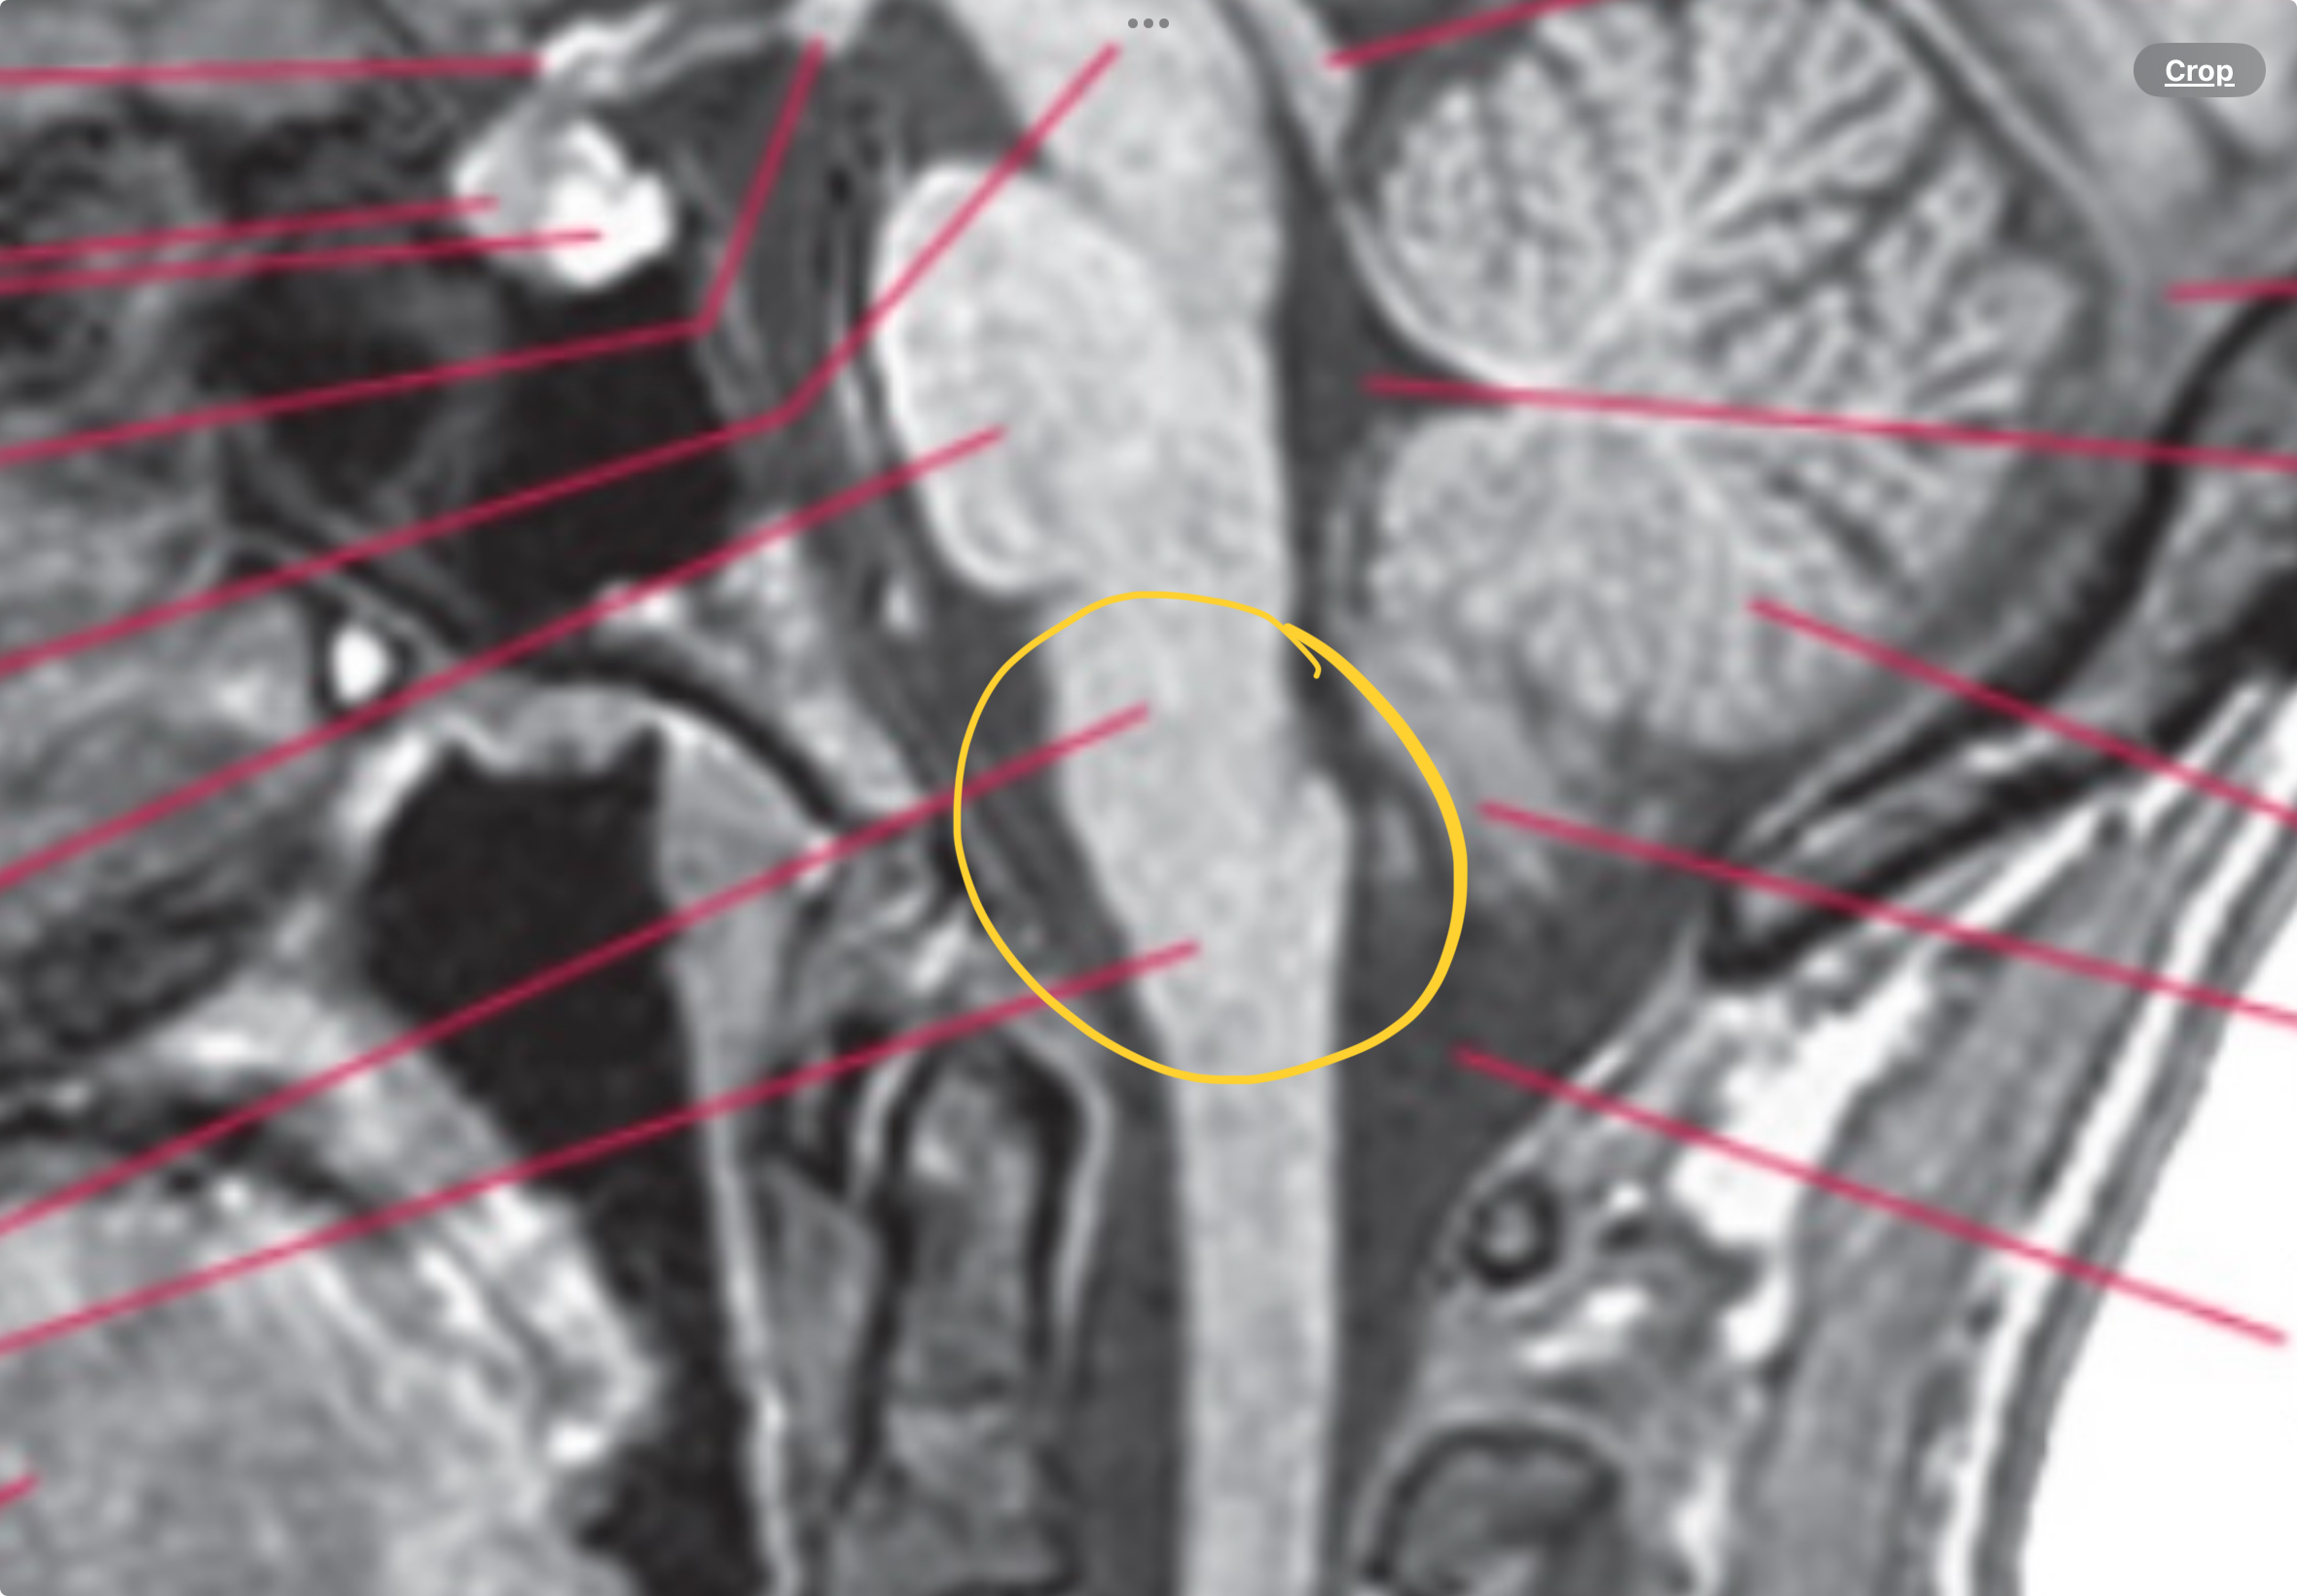

Medulla

Pyramids, part of 4th ventricle, central canal/ spinal cord